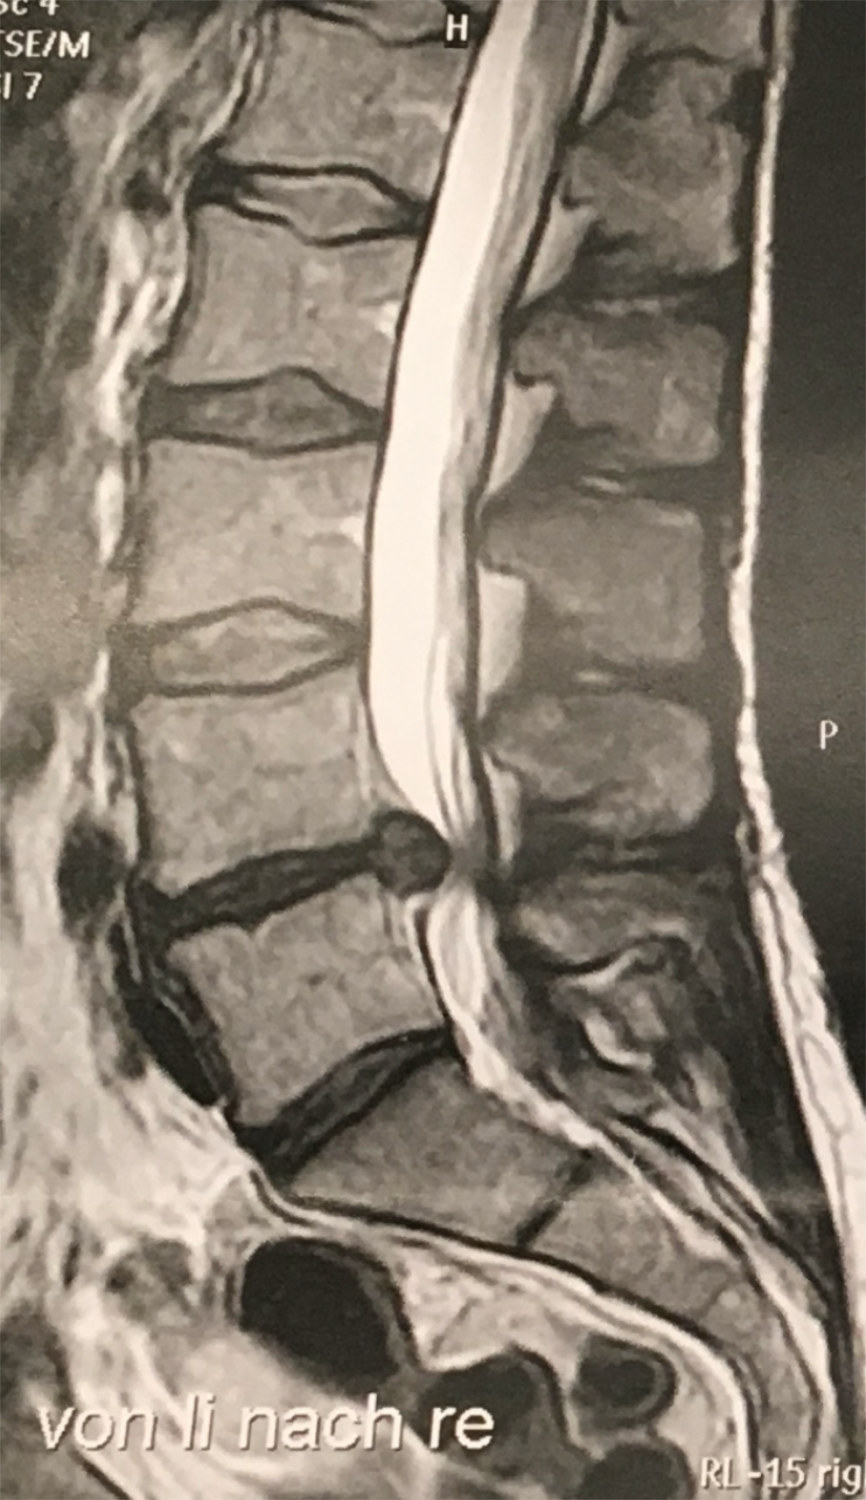

Las hernias discales se producen con mayor frecuencia en la columna lumbar, con menor frecuencia en la columna cervical y sólo en raras ocasiones en la columna torácica.

El quiropráctico realiza un diagnóstico basado en el historial médico del paciente y los resultados de los exámenes clínicos. También suelen realizarse radiografías o resonancias magnéticas como parte de los exámenes clínicos.

El tratamiento suele producir una mejoría inmediata de los síntomas. Las investigaciones realizadas con equipos de última generación (resonancia magnética) han demostrado que la hernia discal no siempre se regenera, pero que puede normalizarse la libertad de movimiento y la ausencia de síntomas. Esto se ve respaldado por otros estudios, como se ha mencionado anteriormente, que indican que los pacientes pueden estar absolutamente libres de síntomas (sin dolor, etc.) incluso con una hernia discal.